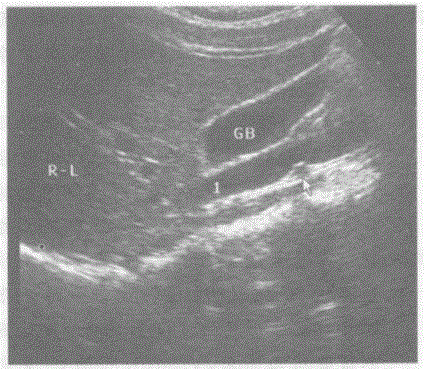

请回答1和箭头所指部位声像图的断面解剖名称:A.下腔静脉和右肾动脉B.下腔静脉和左肾动脉C.腹主动脉和左肾静脉D.腹主动脉和右肾静脉

问题 请回答1和箭头所指部位声像图的断面解剖名称:

选项 A.下腔静脉和右肾动脉 B.下腔静脉和左肾动脉 C.腹主动脉和左肾静脉 D.腹主动脉和右肾静脉

答案 A